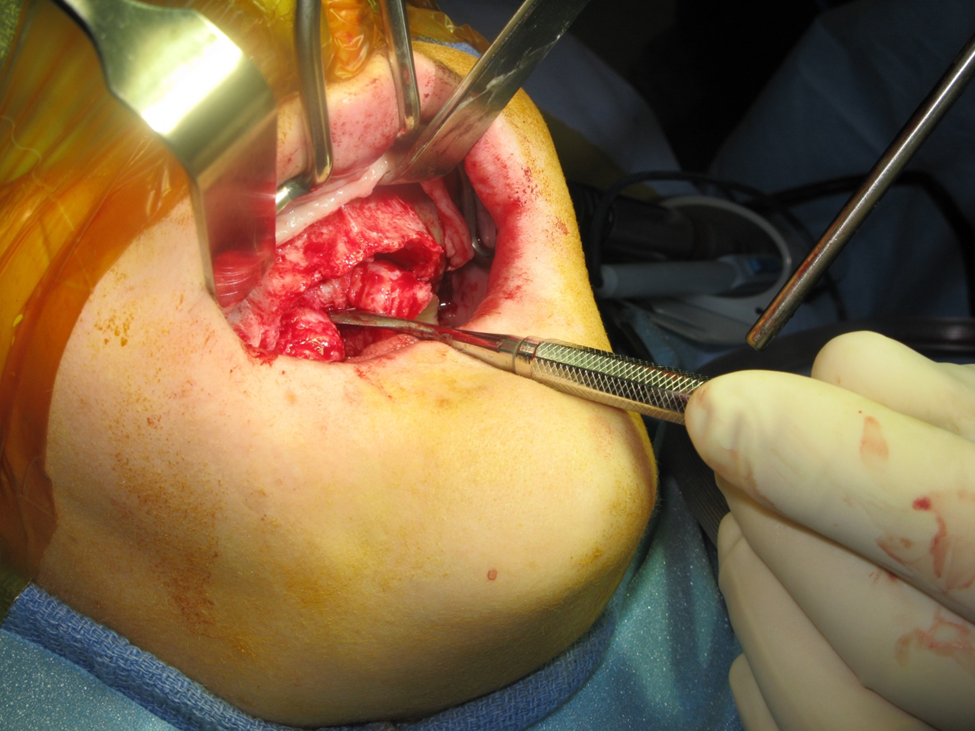

Figure 1a. Photo demonstrating Class V ridge after flap elevation. This was a 38-year-old female, who demonstrated significant atrophy in the buccal-lingual dimension. The vertical height was also insufficient for implant placement.

Figure 1b. Completion of bilateral sinus lift dissection. Note elevation of full palatal flap. This is necessary to relieve tension on the wound closure in addition to labial and buccal full muco-periosteal reflection as high as the infraorbital rims. The periosteum is then scored to allow flap mobilization. The sinus lifts were performed in the standard fashion.